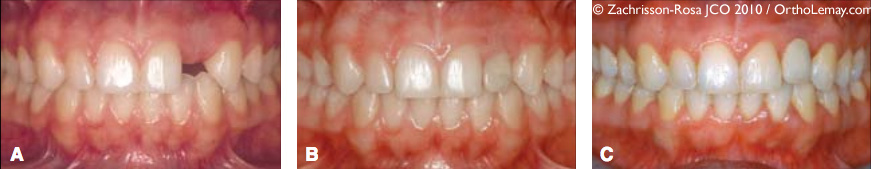

Illustration 2

Exemple de substitution des canines pour des incisives latérales manquantes

(A) Adolescente ayant une incisive latérale supérieure droite manquante (anodontie) et l’incisive latérale gauche étroite et difforme.

(B) Après le traitement d’orthodontie ayant rapproché la canine droite contre l’incisive centrale et l’ayant modifiée par meulage sélectif (améloplastie), une facette de porcelaine fut placée sur la latérale gauche difforme.

(C) 19 ans plus tard, il n’y a aucun signe d’infraclusion, la gencive est intacte et de couleur et formes normales et les papilles gingivales sont intactes (Zachrisson et Rosa, 2010).

Illustration 1

Exemple de changements possibles avec le temps affectant une couronne temporaire

(A) Femme de 20 ans chez qui l’espace de la latérale supérieure gauche manquante a été ouvert pour y poser un implant dentaire.

(B) Couronne temporaire en place.

(C) Après seulement 5 ans, une infraclusion est déjà visible sur la couronne implanto-portée à cause de l’éruption continue des dents adjacentes, rendant le contour gingival inesthétique (Zachrisson et Rosa, 2010).